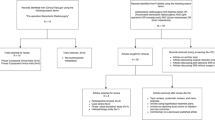

This technique has only recently been assessed in clinical studies. Our group published the results of a phase I prospective trial evaluating the toxicity and efficacy of hypofractionated proton CSI in patients with LM [68]. The regimen was well tolerated, with 2 of 20 evaluable patients experiencing dose-limiting toxicities, all of which resolved without medical intervention [68]. Despite the small sample size, proton CSI did provide durable CNS disease control in some patients, with 4 of 21 individuals being free of CNS progression 12 months after therapy [68]. A subsequent phase II trial, NCT04343573, is currently underway comparing proton CSI against involved-field photon RT including WBRT and/or focal spine RT in patients with LM from breast cancer or non-small cell lung cancer [69].